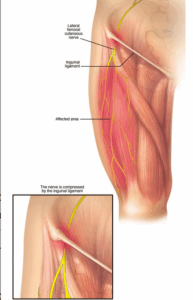

Meralgia paresthetica

Meralgia paresthetica is a condition that causes tingling, numbness and burning pain in the outer thigh. It's caused by compression of the nerve that provides feeling to the skin covering the thigh.